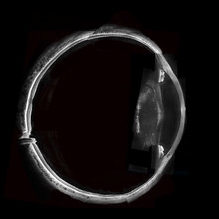

Whole Eye OCT

Jan 4 2019 by Netan Choudhry, MD, FRCS(C) FASRS

Swept-Source OCT montage of a 45-year-old male with Alports disease and posterior subcapsular cataract.

Photographer: John Golding BA, Vitreous Retina Macula Specialists of Toronto

Imaging device: Topcon DRI Triton

Condition/keywords: Alports disease, optical coherence tomography (OCT), swept source